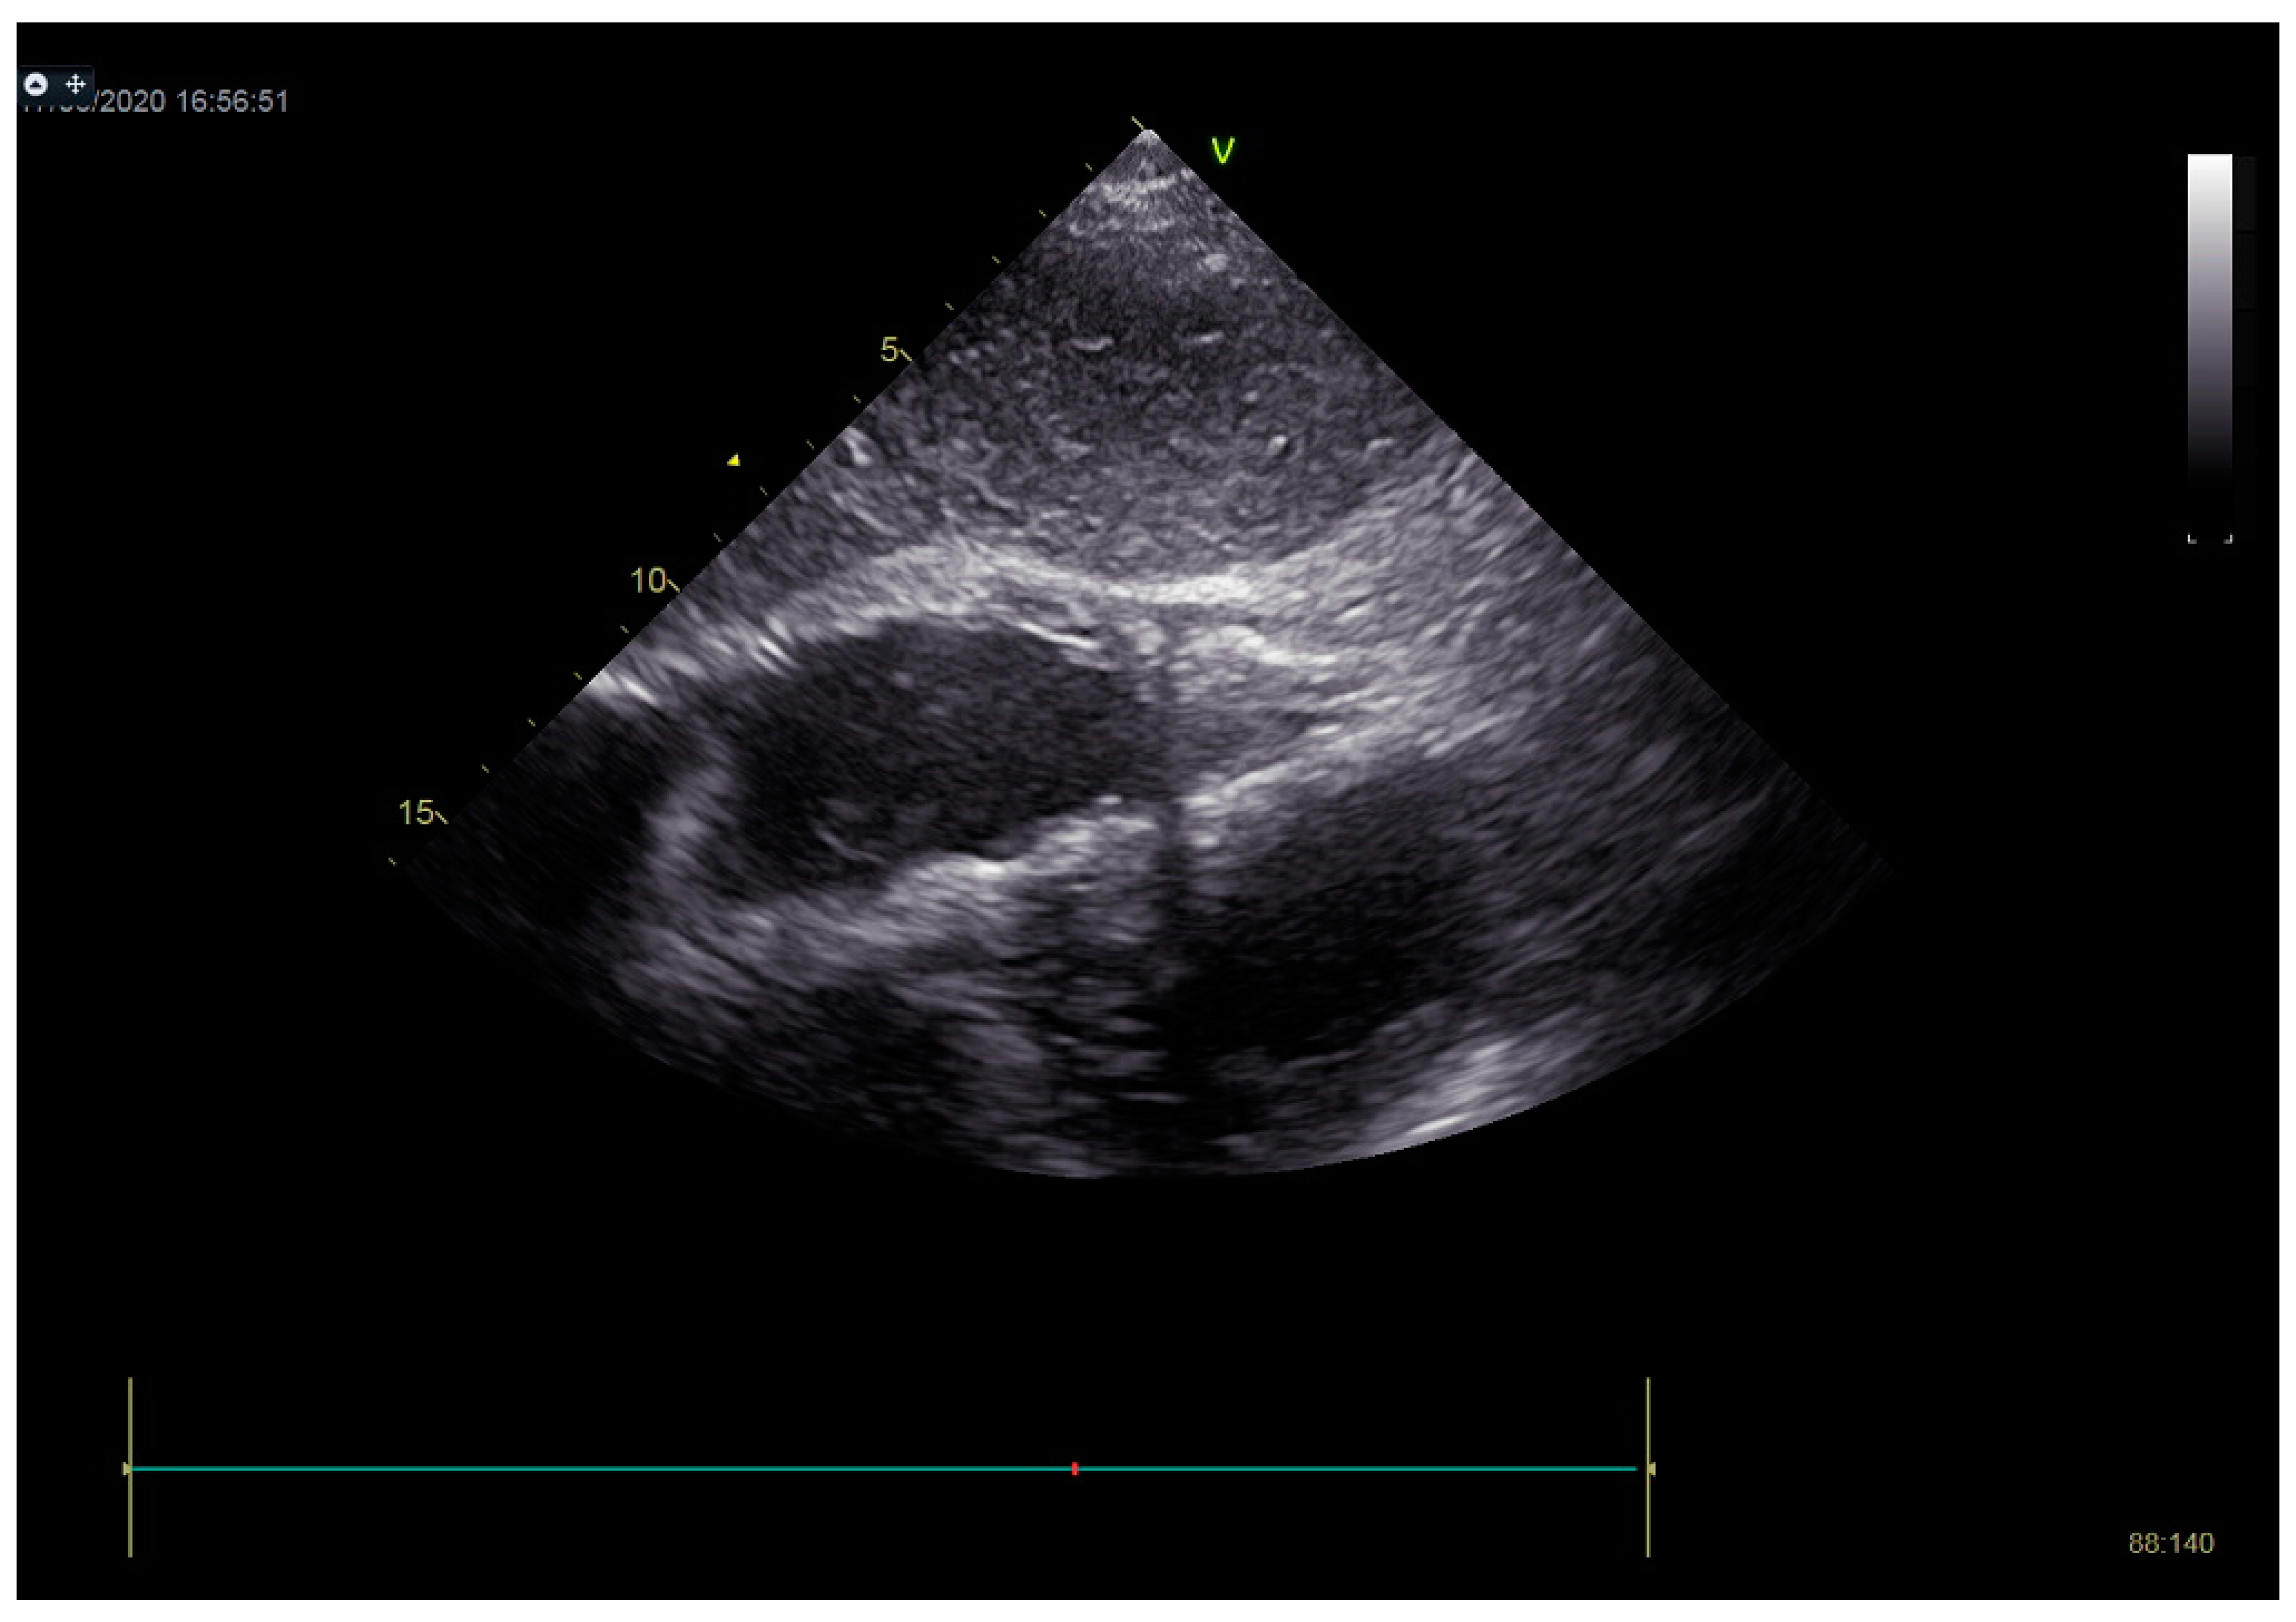

As a result, the patient was referred to a specialized medical institution. Upon admission, the patient was conscious, confused, hypotensive (TA 80/50 mmHg), with a heart rate of about 110/min, and showing clinical signs of hypoperfusion and cardiogenic shock, Killip IV. The medical staff administered sedation, inserted an endotracheal tube, and placed her on invasive mechanical ventilation. The patient was given crystalline solutions, inotrope, and vasopressor medication. An urgent echocardiographic examination was performed due to a rough systolic murmur over the precordium. It revealed akinesia of all medioapical segments of the left ventricle and akinesia basally inferior, where the myocardium was fibrously altered. Other hyperkinetic basal segments formed a dynamic obstruction of the left ventricular outflow tract (LVOTO) with turbulent flow and moderate mitral regurgitation (Figure 2 and Figure 3). The maximum gradient above the LVOT was 160 mmHg (Figure 4). The aortic valve area was 1.8 cm2 (Figure 5). The ejection fraction of the left ventricle (LVEF) was estimated to be 25%. The examination also revealed pericardial effusion with separation between pericardial layers along the right ventricle and atrium of up to 1.2 cm, but without any signs of tamponade.

Figure 2.

Echocardiography registered basal hyperkinetic segments of the left ventricle and formed a dynamic obstruction of the left ventricular outflow tract (a—LVOT, b—cuspi anterioris valvulae mitralis, c—aortic valve).